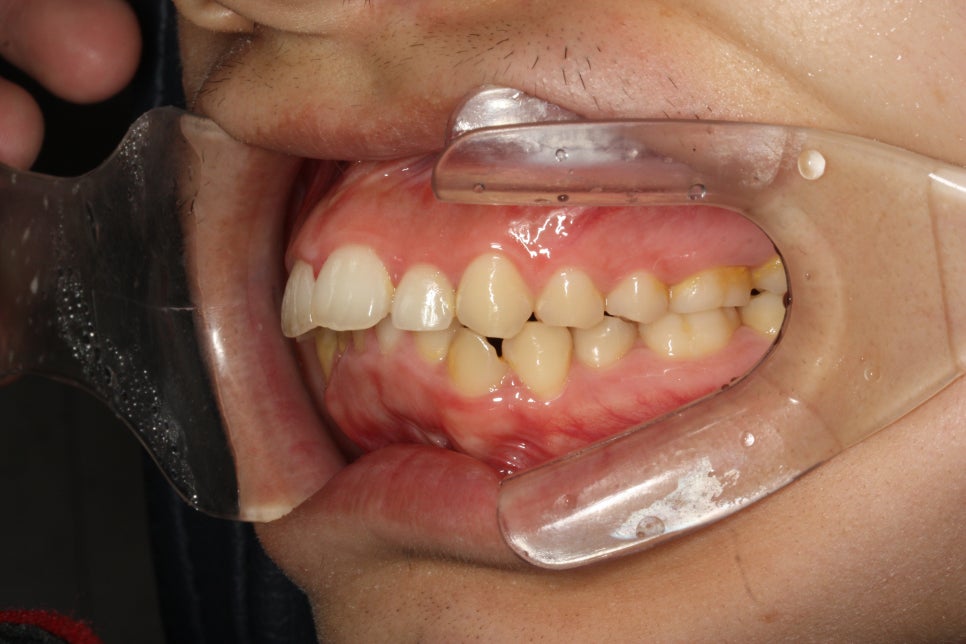

앞니가 많이 돌출되어 있는 환자분이었습니다.

어금니와 송곳니 관계를 보면 발치를 하는 것이 치료를 하는 입장에서 훨씬 편할 수 있는 상태였습니다.

환자분은 심한 무턱과 단안모의 형태를 가진 안모의 소유자였습니다.

이런 분들은 자칫 입이 과하게 들어가면 안모가 많이 안좋아질 수 있죠.

환자분과 상담 후 비발치로 최대한 입을 넣기로 했습니다.